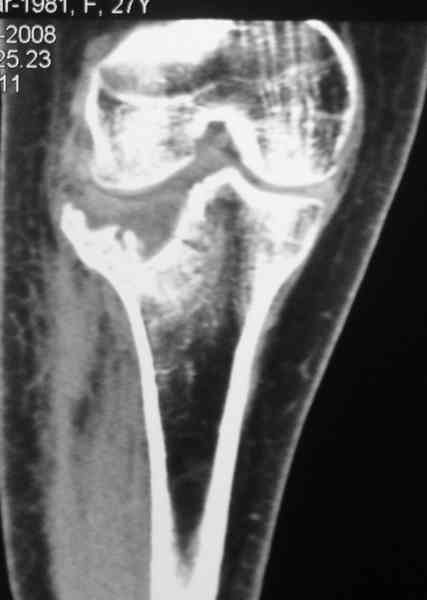

Re: Застарелый перелом 41С3

Уважаемый Абдурашид. Если нет противопоказаний , то из оперативных способов, я бы рекомендовал следующие: Полное замещение наружного мыщелка аллотрансплантатом либо открытая репозиция с элевацией и замещение дефекта ауто или аллокостью. В Ваших условиях , я бы рекомендовал второй способ. Во-время элевации необходимо разъединить фрагменты со стороны сустава ( надсечь скальпелем по линиям перелома, а затем тонким остеотомом их разъединить. При помощи долота произвести неполную остеотомию ( захватите не менее 1,5 - 2 см губчатой кости и поднять фрагменты, визуально отрепонировать и фиксировать 2-3 спицами. Дефект заместить костным ауто или аллатрансплантатом. Окончательная стабилизация пластиной ( лучше с угловой стабильностью, либо АВФ - позволит спокойно устранить угловую деформацию.

Недавно поступила больная через 1,5- 2 месяца.